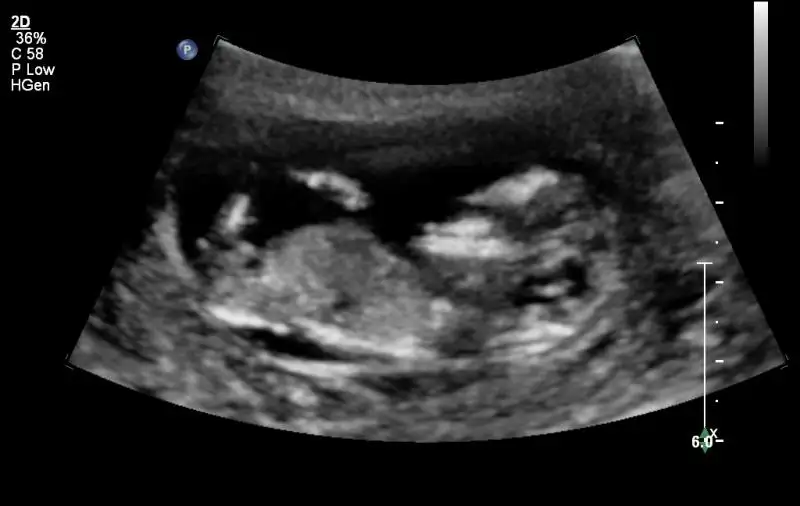

Kızlar cinyetini öğrenen oldu mu? bide kaçıncı haftada öğrendiniz? ben dün dr.a gittim 12 haftalıkmış ve kıza benziyor dedi. yanılma payı olur mu acaba, hani tahmin için bile erken bi hafta diye düşünüyorum

ben dün öğrendim, 12+0 yani 12. haftamı tam bitirdiğimde öğrenmiş oldum. doktorum hiç bir zaman %100 diyemem ama kız görüyorum dedi. muhtemelen değişmez, değişen çok az kişi gördüm.

bence güvenme 12 haftada gittik kıza benziyor dedi 13. haftada gittiğimizdede erkeğe benziyor dedibende geçen geldiğimizde kız demiştiniz ama dedim o zaman ben bişiy bilmiom deyip güldü 16. haftayı bekleyin net söyleyeyim

ya ama pipiye benzer hiç bir şey yok dedi, sonradan çıkar mı ki pipi

Benim ilk bebeğim 11. haftanın sonunda belli olmuştu . Ama kesin olarak 16 da söylüyorlar.

Bu bebeğim hala belli değil . Belki haftaya cuma ikili testte belli olur